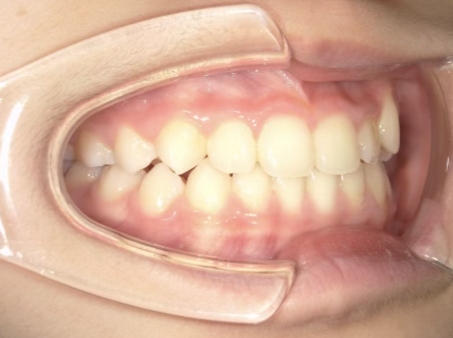

治療中④ 小4:10y1m

左上3が八重歯で萌出中